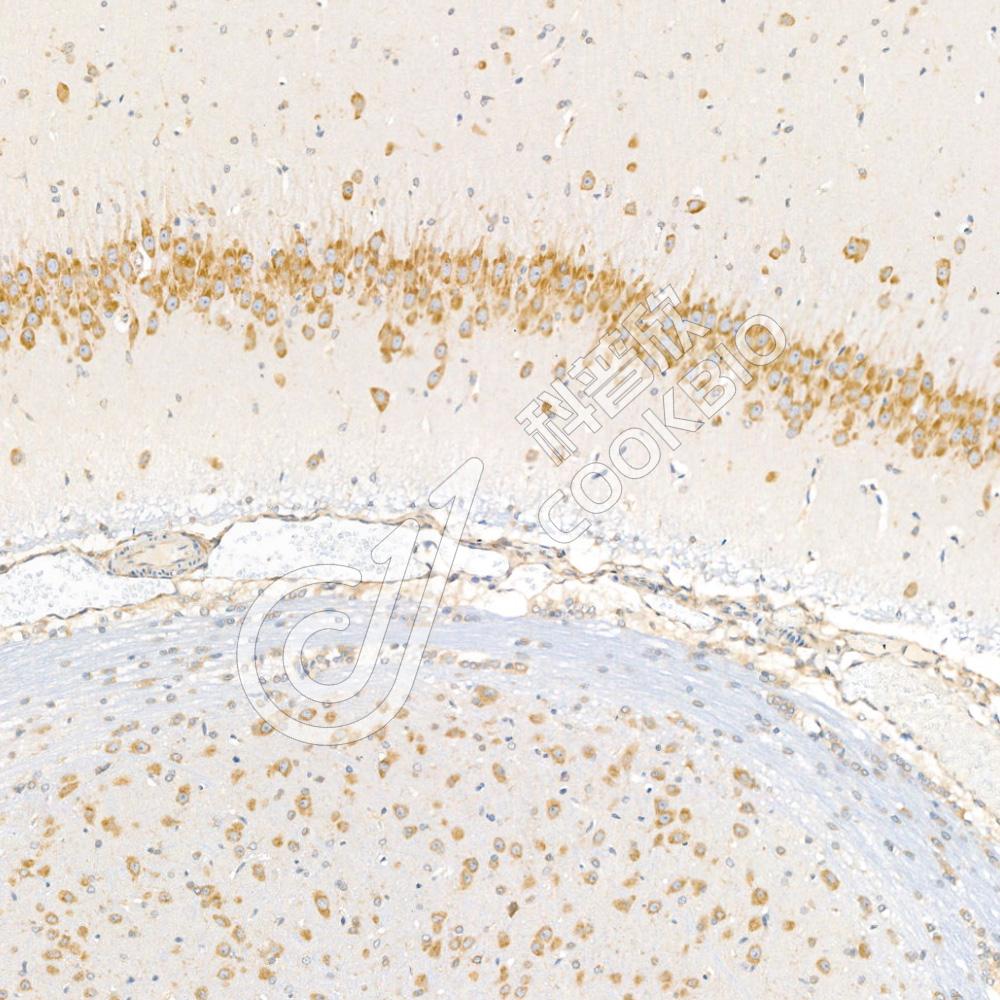

IHC检测Flt3/CD135蛋白(货号 K1334074).

样品: 大鼠胎盘, 4%多聚甲醛 (货号KSG1101) 固定12-24小时.

抗原修复: 柠檬酸抗原修复液(干粉, pH 6.0) (KSG1201), 98℃, 20分钟.

—抗: 1: 2500稀释, 4℃ 孵育过夜.

二抗: S-vision免疫组化多聚二抗(山羊抗兔),即用型 (货号KB3906), 室温孵育20分钟.